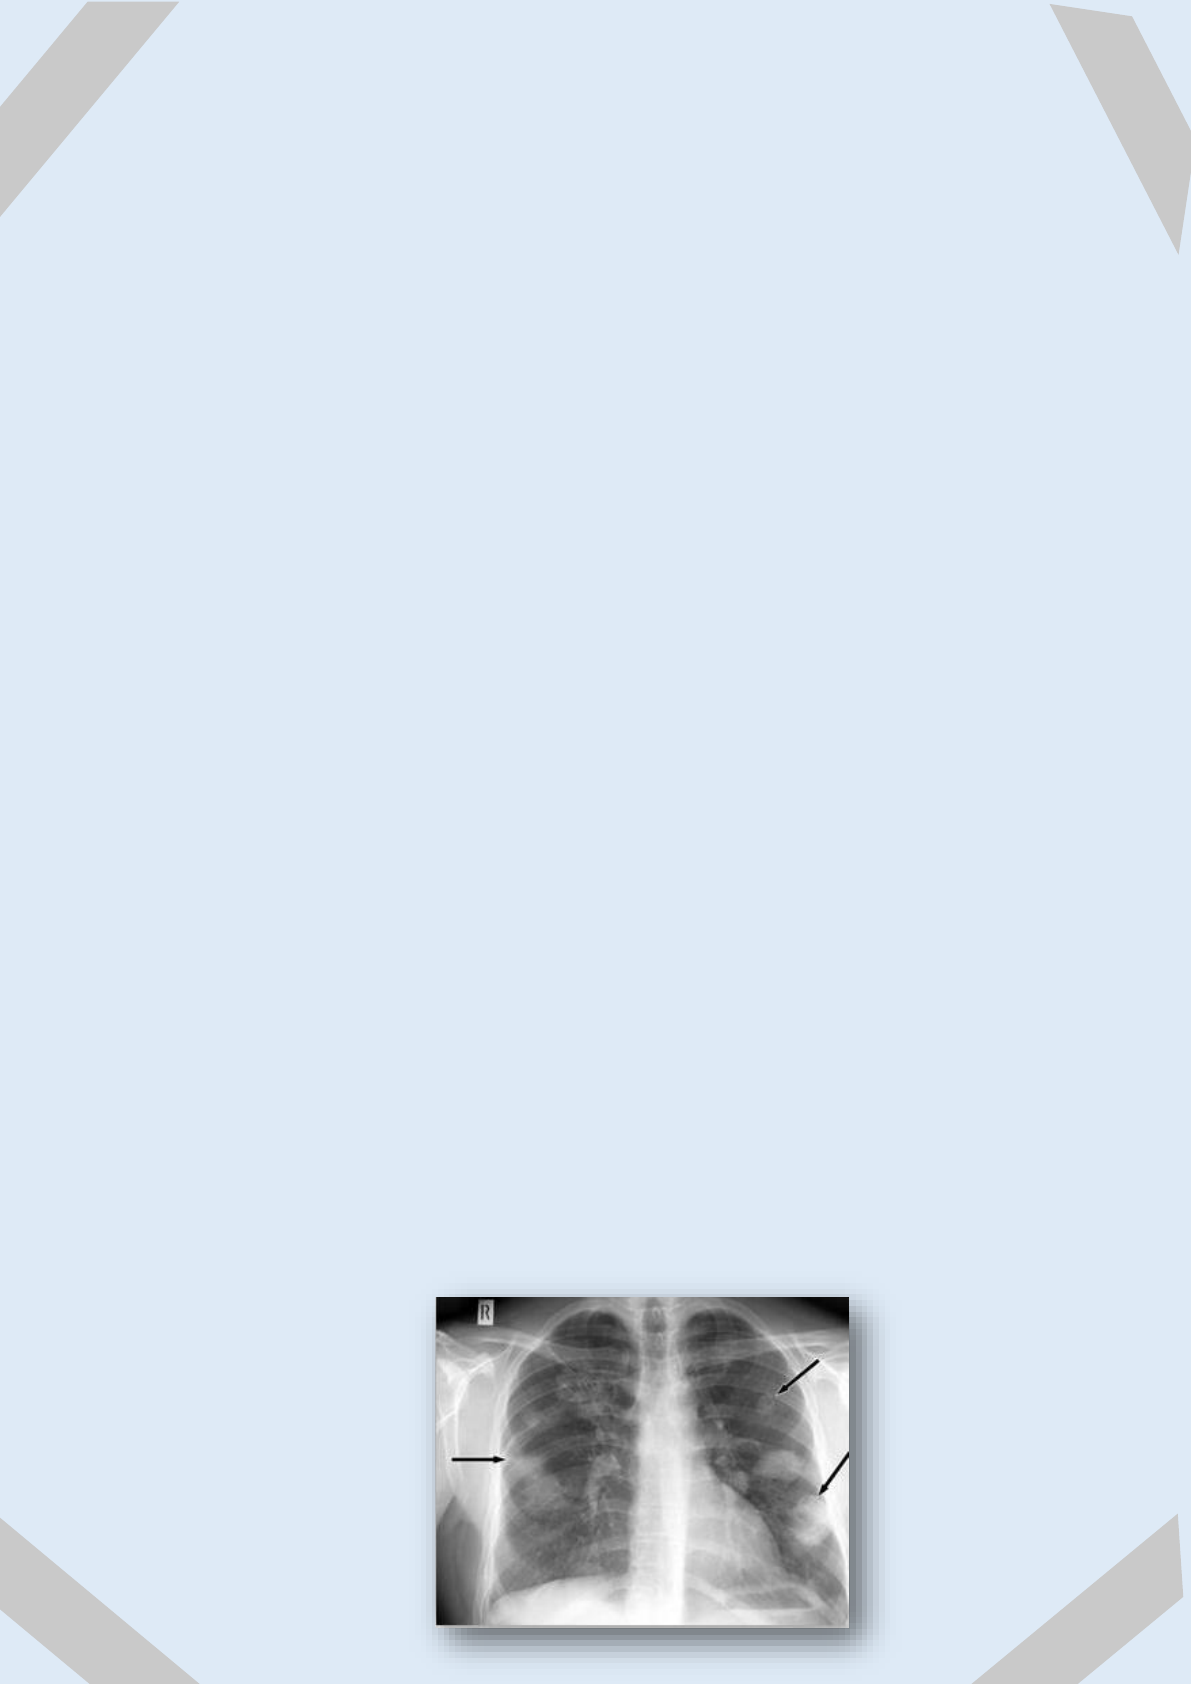

SÍNDROME DE DERRAME

PLEURAL:

Acumulación anormal de líquido en el espacio pleural

(membrana que recubre al pulmón).

DIAGNÓSTICO:

Las pruebas de detección o diagnósticas, sirven para documentar

la presencia de líquido pleural y determinar su causa.

- Radiografía de tórax, que nos servirá para verificar el estado

funcional y anatómico de dicha estructura.

- Análisis del líquido pleural, comprobando su cantidad y partes

que afecta.

- Angiotomografía, produce imágenes de los vasos sanguíneos y

tejidos cerca del pulmón.